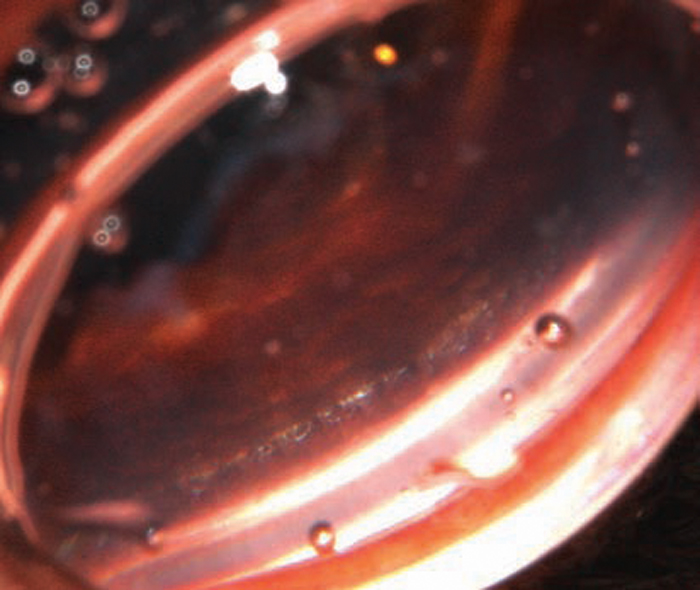

Endoscopic photograph showing angle glaucoma in a dog. The pectinate …

Endoscopic photograph showing open angle phacoanaphylactic glaucoma …